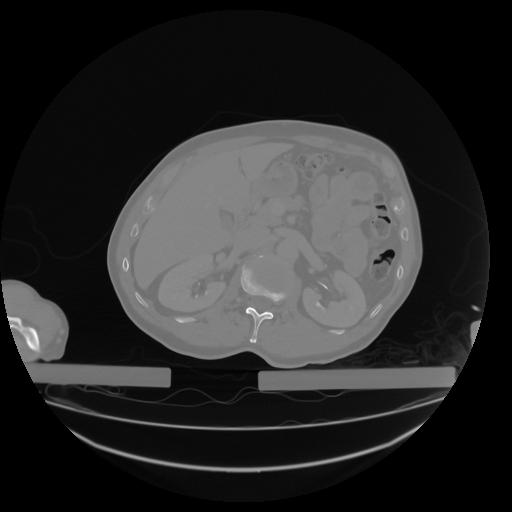

27 CUERPO,CE,Axial,3.0,CUERPO,,